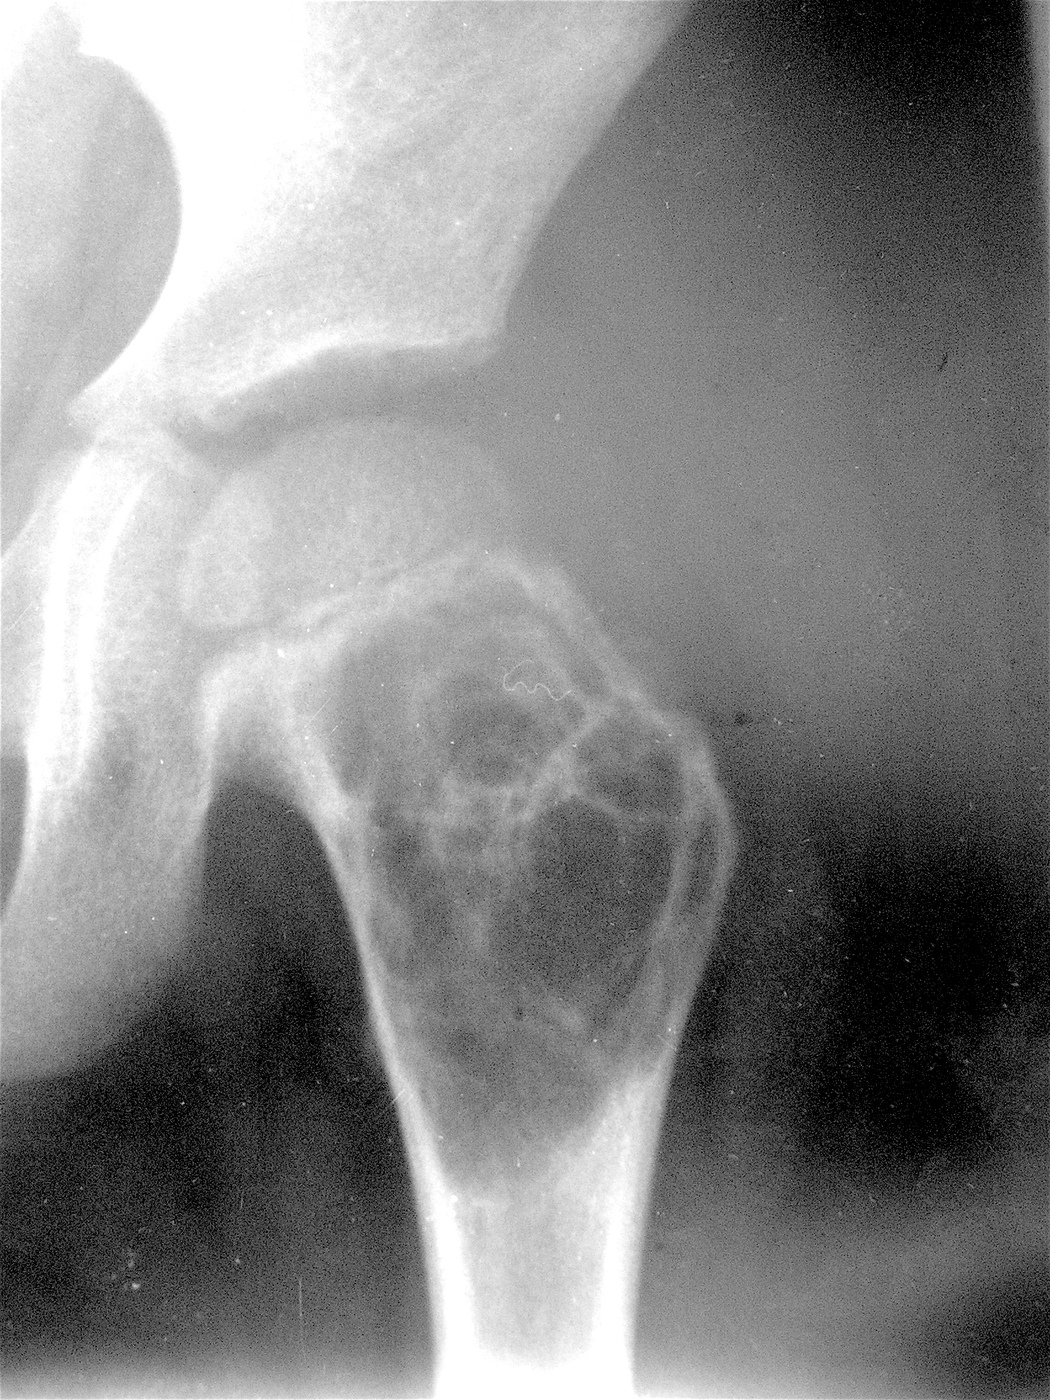

Закрытый патологический перелом шейки левой бедренной кости и проксимального метафиза бедренной кости на фоне аневризмальной костной кисты.

Аллопластика материалом «Лиопласт».